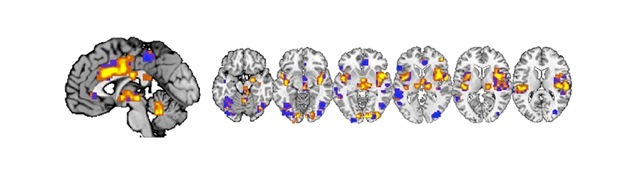

Cercetătorii americani au analizat cu ajutorul unui computer imaginile creierelor a 114 persoane, realizate cu un dispozitiv de scanare atunci când voluntarii erau expuşi în faţa unor intensităţi diferite dureroase, cauzate de aplicarea unor stimuli termici pe piele.

Cu ajutorul unui program computerizat, oamenii de ştiinţă au putut să identifice astfel semnătura neurologică a durerii.

„Am descoperit reacţii similare în multe zone ale creierului care corespund intensităţii durerii resimţite de acele persoane care răspuns la căldura aplicată”, explică Tor Wager.

Şi, contrar aşteptărilor, aceste semnături cerebrale ale durerii nu erau specifice fiecăruia dintre participanţii la acest studiu, ci erau similare între ele.

Astfel, cercetătorii au putut să prezică cu un grad de acurateţe de 90% până la 100% nivelul durerii pe care o persoană o resimte, atunci când aceasta era confruntată cu intensităţi diferite ale unor stimuli termici aplicaţi pe piele.

Savanţii americani au observat totuşi că semnătura neurologică arăta o scădere a durerii la persoanele supuse aceloraşi teste cu stimuli de căldură, dar care luau un analgezic.